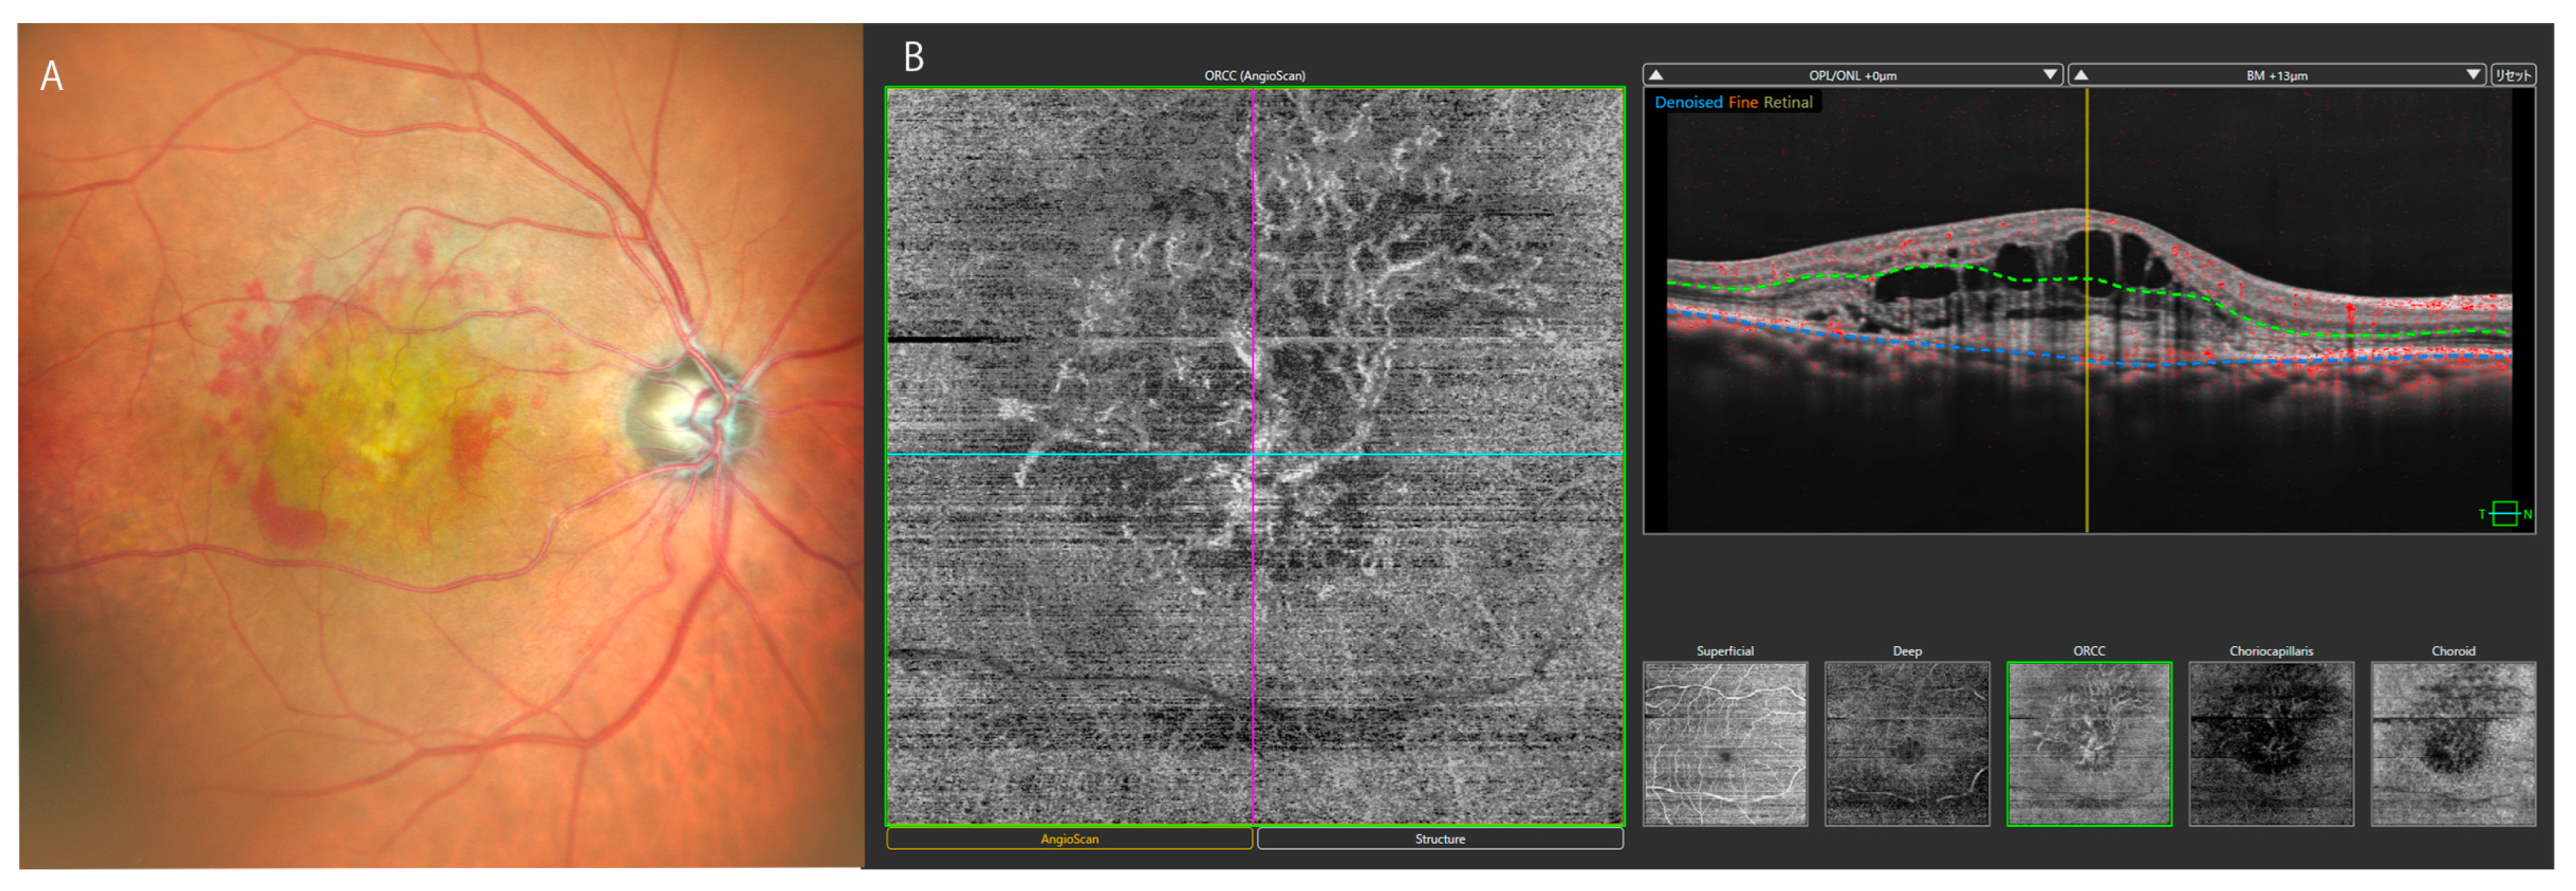

3.3. Diabetic Retinopathy

- Ishibazawa, A.; Nagaoka, T.; Takahashi, A.; Omae, T.; Tani, T.; Sogawa, K.; Yokota, H.; Yoshida, A. Optical Coherence Tomography Angiography in Diabetic Retinopathy, A Prospective Pilot Study. Am. J. Ophthalmol. 2015, 160, 35–44.e1. [Google Scholar] [CrossRef]

- Salz, D.A.; de Carlo, T.E.; Adhi, M.; Moult, E.; Choi, W.; Baumal, C.R.; Witkin, A.J.; Duker, J.S.; Fujimoto, J.G.; Waheed, N.K. Select Features of Diabetic Retinopathy on Swept-Source Optical Coherence Tomographic Angiography Compared with Fluorescein Angiography and Normal Eyes. JAMA Ophthalmol. 2016, 134, 644–650. [Google Scholar] [CrossRef]

- Horie, S.; Ohno-Matsui, K. Progress of Imaging in Diabetic Retinopathy-From the Past to the Present. Diagnostics 2022, 12, 1684. [Google Scholar] [CrossRef]

- Waheed, N.K.; Rosen, R.B.; Jia, Y.; Munk, M.R.; Huang, D.; Fawzi, A.; Chong, V.; Nguyen, Q.D.; Sepah, Y.; Pearce, E. Optical coherence tomography angiography in diabetic retinopathy. Prog. Retin. Eye Res. 2023, 97, 101206. [Google Scholar] [CrossRef] [PubMed]

- Schwartz, R.; Khalid, H.; Sivaprasad, S.; Nicholson, L.; Anikina, E.; Sullivan, P.; Patel, P.J.; Balaskas, K.; Keane, P.A. Objective Evaluation of Proliferative Diabetic Retinopathy Using OCT. Ophthalmol. Retin. 2020, 4, 164–174. [Google Scholar] [CrossRef]